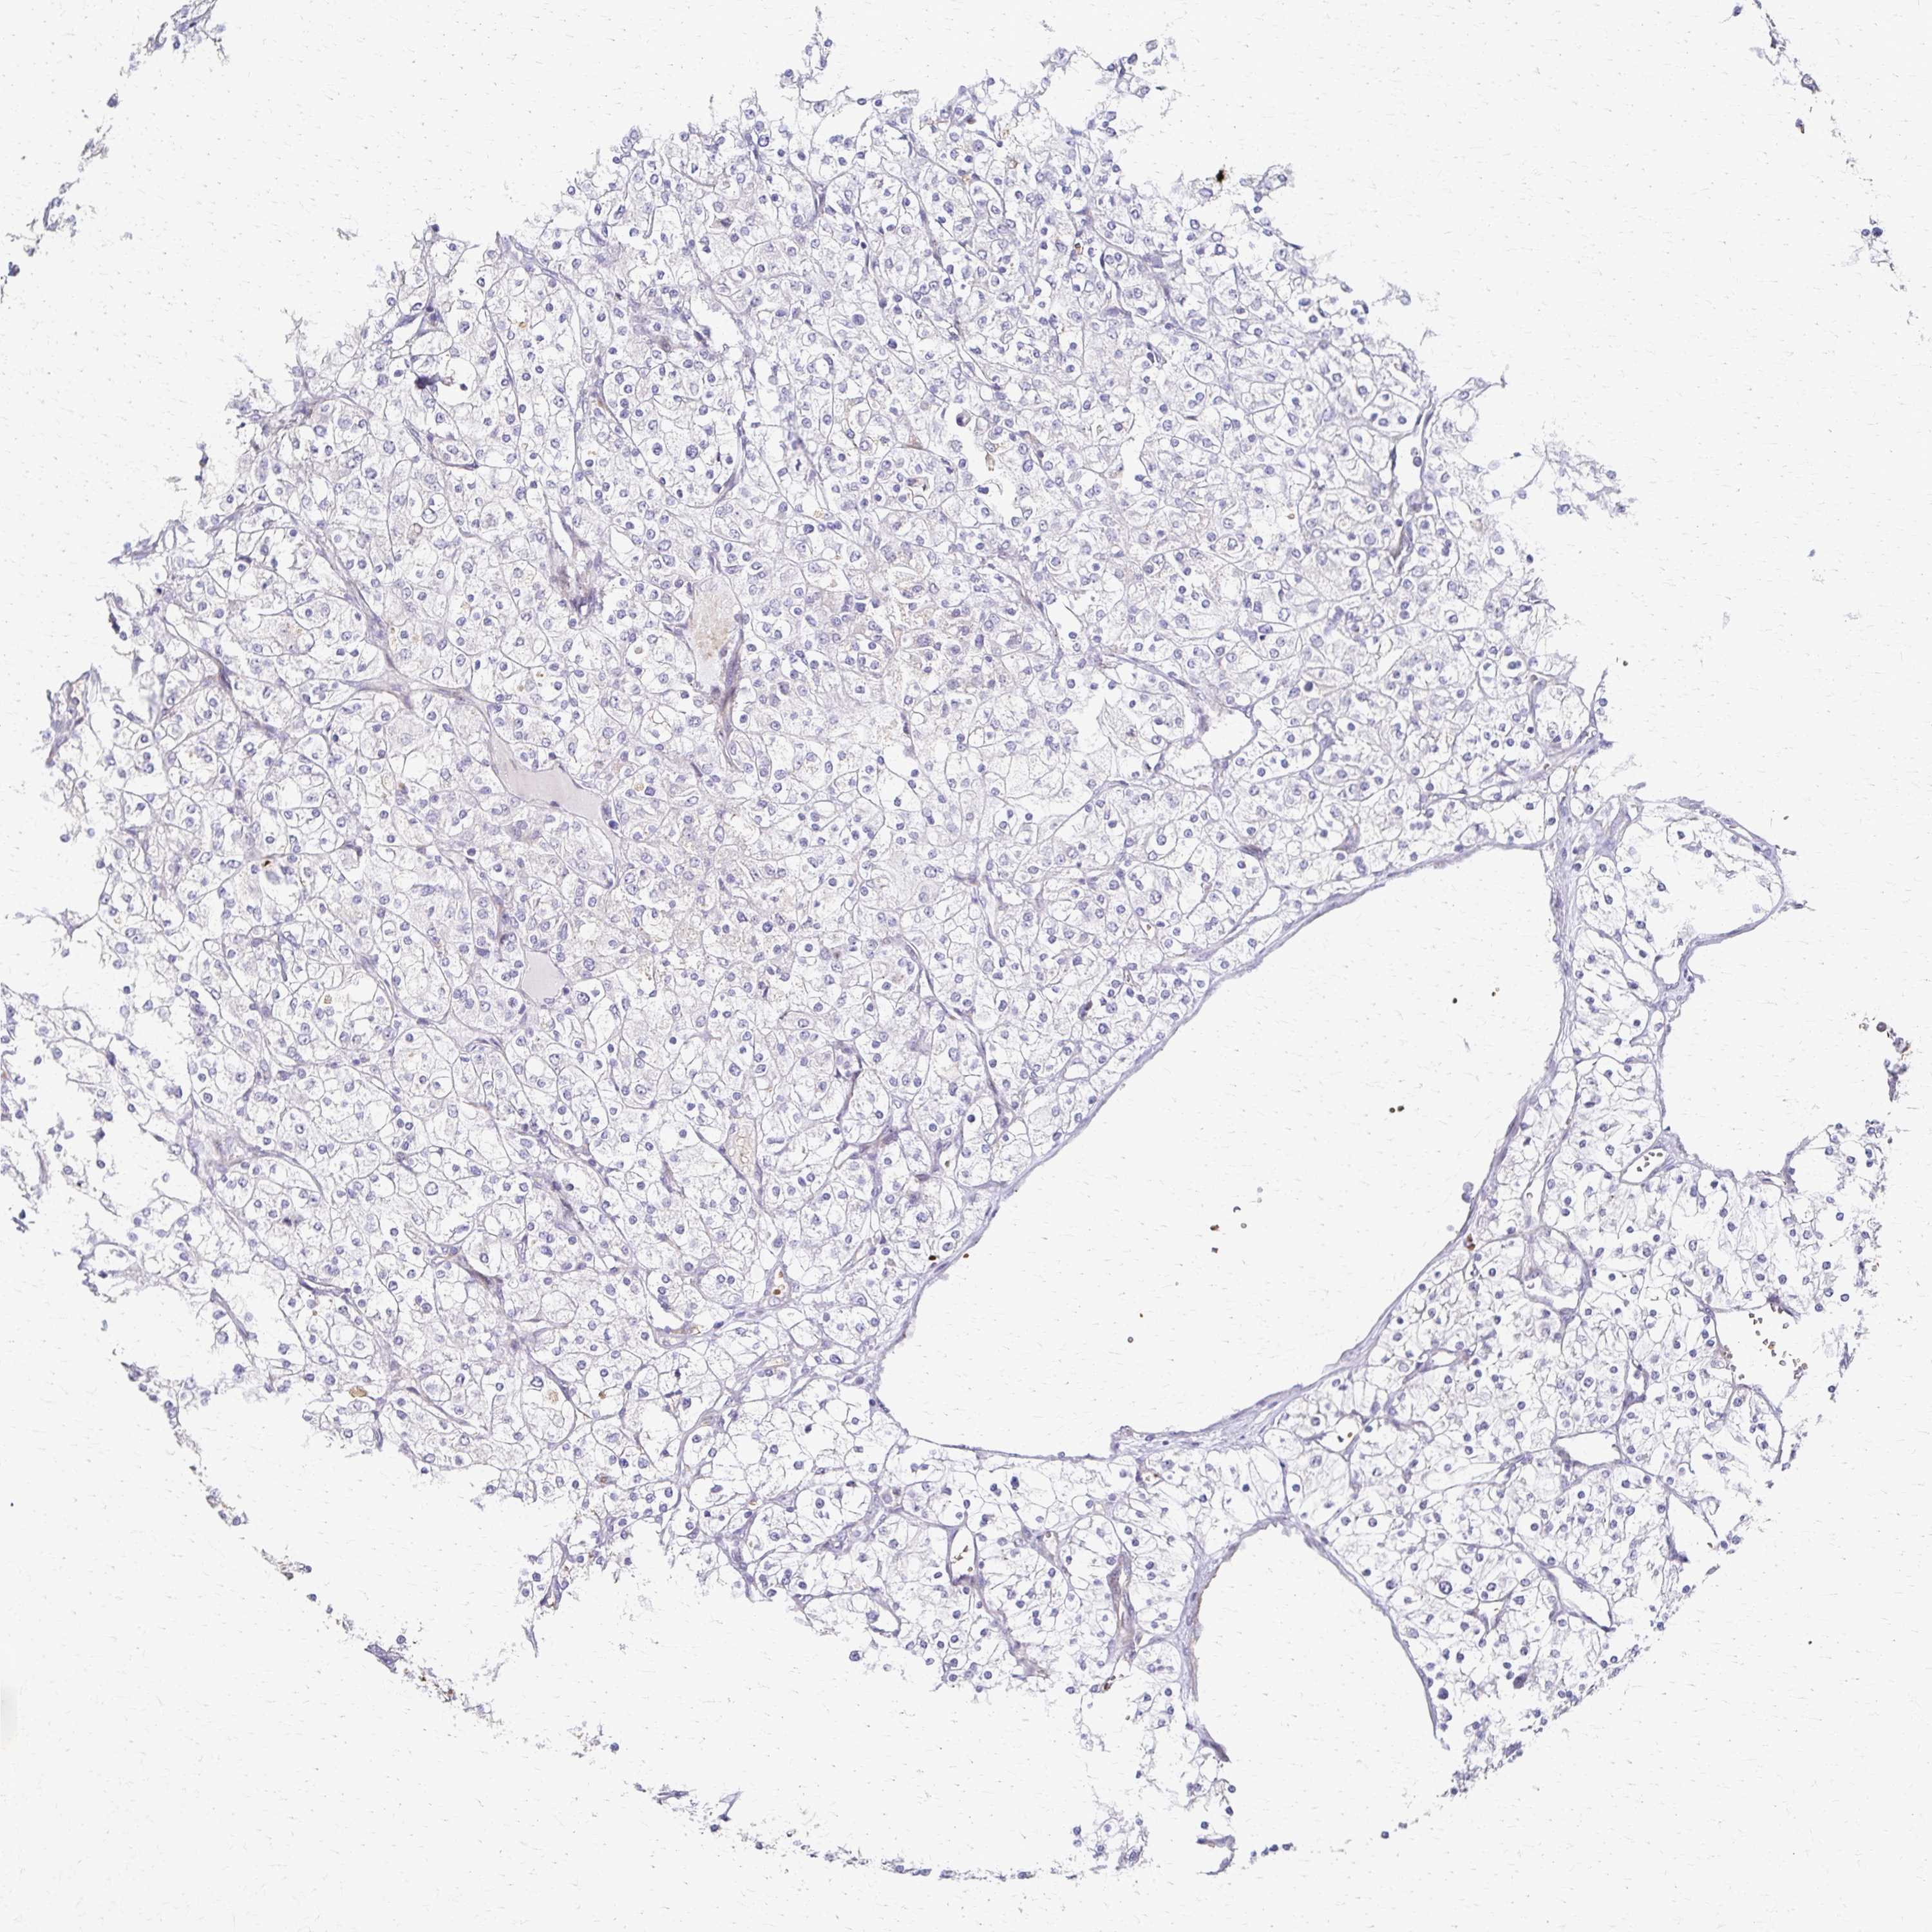

CANCER RENAL CANCER Show tissue menu

Renal cancer

Kidney chromophobe